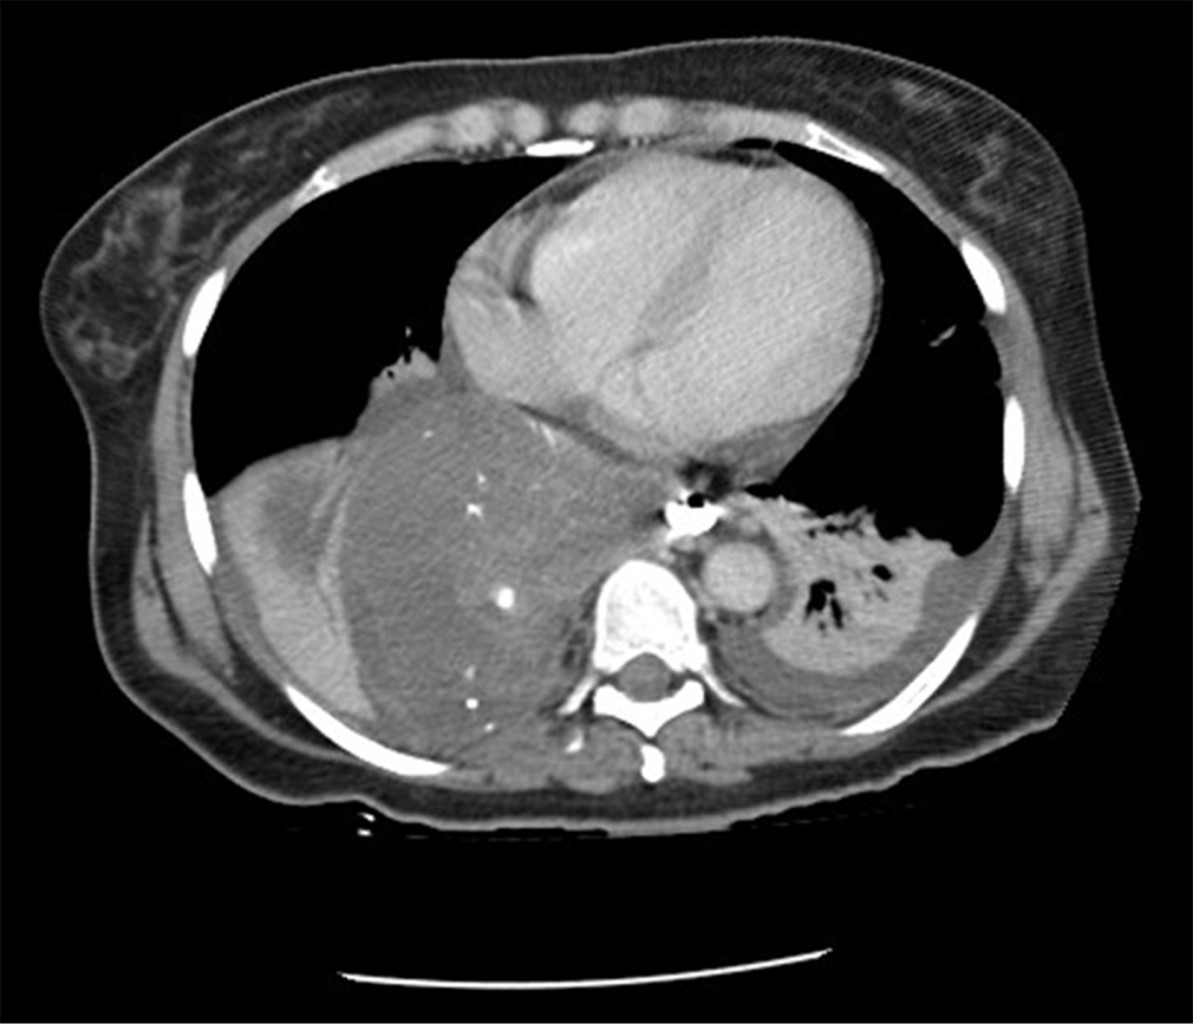

Mujer de 54 años con antecedente de hipertensión arterial sistémica de 16 años de evolución en tratamiento médico con losartán 50 mg cada 24 horas en buen control, antecedente de histerectomía total abdominal hace 14 años por miomatosis uterina, colecistectomía laparoscópica hace cuatro años por colecistitis crónica litiásica ambas sin complicaciones aparentes, inicia su padecimiento de 36 horas de evolución con dolor torácico importante, fiebre no cuantificada y ataque al estado general, por lo que acude a su valoración en nuestra unidad, al interrogatorio dirigido refiere un historial de cinco años de sintomatología caracterizada por disfagia a la ingesta de alimentos sólidos. En la exploración física se encuentra una paciente en malas condiciones que presenta taquicardia de 120 pulsaciones por minuto, hipotensión de 90/60 mmHg, frecuencia respiratoria de 23 respiraciones por minuto, temperatura de 36.5 oC, palidez de tegumentos generalizada, a la auscultación del tórax lado derecho con disminución de los ruidos respiratorios con matidez a la percusión e incremento de las vibraciones vocales, el abdomen es plano, blando depresible no presentando datos de irritación peritoneal. En la analítica de laboratorio destaca una hemoglobina de 16.6 g/dl, hematocrito de 49.68%, leucocitos de 18 cel/mm3, neutrófilos de 89%. Se realizó una tomografía toracoabdominal, la cual mostró un tumor dependiente del esófago distal asociado con líquido libre en tórax y salida de medio de contraste de la luz del esófago (Figuras 1 y 2). Por el cuadro clínico presentado de perforación esofágica y mediastinitis se decide someter a la paciente a tratamiento quirúrgico.

Los estudios de imagen tales como esofagograma con bario, tomografía computarizada con contraste vía oral, esofagoscopia y el ultrasonido endoscópico son considerados herramientas de gran utilidad diagnóstica en esta patología.17 En el presente caso, la tomografía toracoabdominal reveló un tumor de gran tamaño que se originaba en el tercio inferior del esófago, que tras la administración del medio de contraste por vía oral se demostró una perforación de este órgano, requiriendo la necesidad de intervención quirúrgica de urgencia.